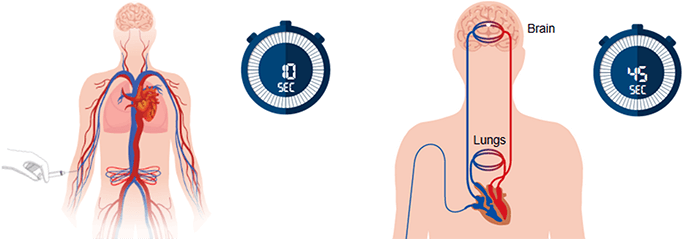

After its injection, the contrast agent travels from the vein through the pulmonary and systemic circulations to the vessels of the brain.

We have mentioned earlier that the CBV calculation is not accurate because of the scan short duration. This is right because a typical perfusion CT requires a contrast injection time of about 10 seconds, followed by only 35 seconds for the bolus to pass from the arm to the brain.